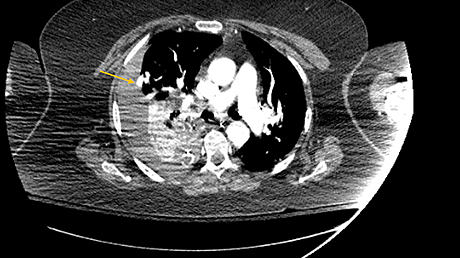

EKG often shows sinus tachycardia, low amplitude QRS complexes, AV or bundle branch block, ST-segment changes, or even Q waves, many of which are non-specific findings. Most of the ECG changes are transient and reversible with the course of time [25-26]. Also, we found out that many of the ECG findings are contrasting between studies. A prospective study by Ison et al. and a retrospective study by Ukimura et al. showed ECG changes in the influenza patients but another prospective study by Kaji et al. in Japan showed normal ECG findings in these patients, which proves that ECG findings are inconsistent [19,27-28]. Elevated creatine kinase isoenzyme MB (CK-MB) fractions and cardiac troponins are also non-specific findings [18-20]. Echocardiography findings can vary from normal to focal or global hypokinesis, pericardial effusions, septal thickness, left, right, or combined ventricular dysfunction with low ejection fraction [29-30]. Endomyocardial biopsy (EMB) has variable sensitivity due to the chances of missing the involved site and the risk-benefit ratio of performing EMB being high [31]. Thus, we can come to the conclusion that clinic correlation is very important in influenza patients to diagnose influenza myocarditis [29-30]. Figure 1 graphically represents the findings of some studies on influenza myocarditis (mortality and number of cases).